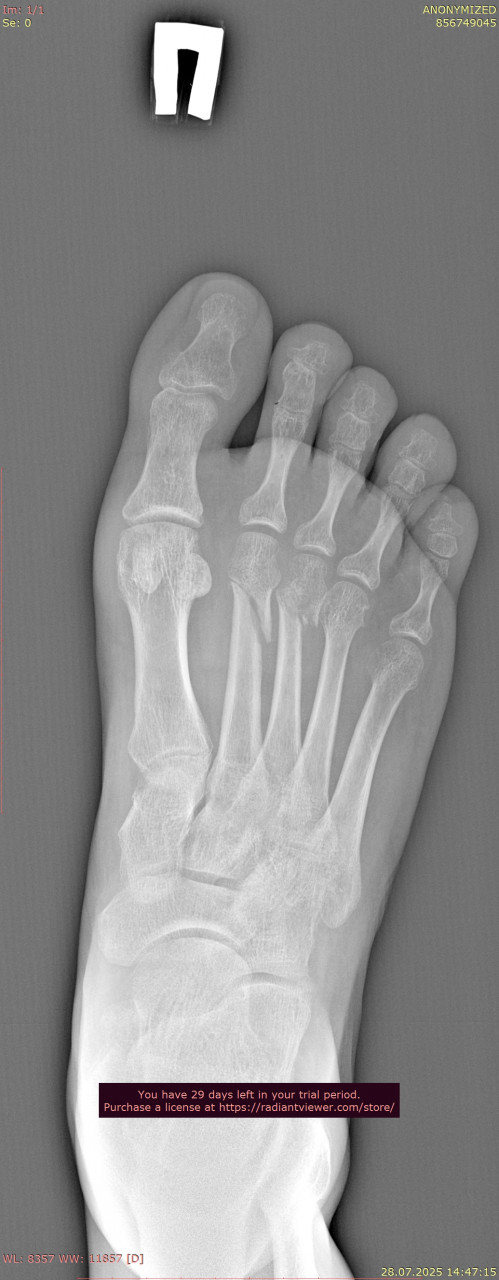

Посмотрите, пожалуйста, снимки стопы и лодыжки от 25.08.2025, перелом был 9 недель назад, 23.08.2025, прикрепляю только прямую проекцию так как лимит сайта 3 файла. Зажили ли переломы, можно ли начинать ходить без дополнительной опоры? Мне 38, мужчина, рост 179, вес 64. Мне говорили что на снимках есть артроз суставов. Подскажите, пожалуйста, насколько он выражен, опасно ли это? Может нужны процедуры, лекарства?

Андрей Павлович, Большое Спасибо Вам за ответ! Прикрепляю недостающий снимок стопы от 23.06.2025, когда был перелом, и снимки лодыжки от 25.08.2025, вчерашние, здесь тоже лимит файлов, снимки лодыжки от даты перелома могу прикрепить в следующем комментарии, и если Вас не затруднит, подскажите, пожалуйста, сильный ли у меня артроз суставов для возраста 38 лет?

Я хожу на ходунках уже 4 недели с 28 07.2025, тогда доктор снял гипс, мне сделали рентген (снимки прилагаю только стопы, рентген голенастопа доктор не сделал в тот день, сказал нет необходимости.) Доктор сказал ходить на ходунках 3 недели, затем ходить без ходунков. Вчера доктор разрешил ходить без дополнительной опоры, опираясь в основном на пятку или на всю стопу. Боли нет, но я боюсь не перегрузит ли токая ходьба лодыжку там же тоже перелом, или там уже хорошая консолидация по снимкам от 25.08.2025? И насколько приемлем такой способ ходьбы, ведь пальцы не сгибаются, я просто переставляю ногу. Как думаете, долго ли нужно так ходить? Доктор сказал принимать Остеогенон, не может ли он усилить артроз? я читал что он может способствовать образованию остеофитов в суставах. Заранее спасибо!